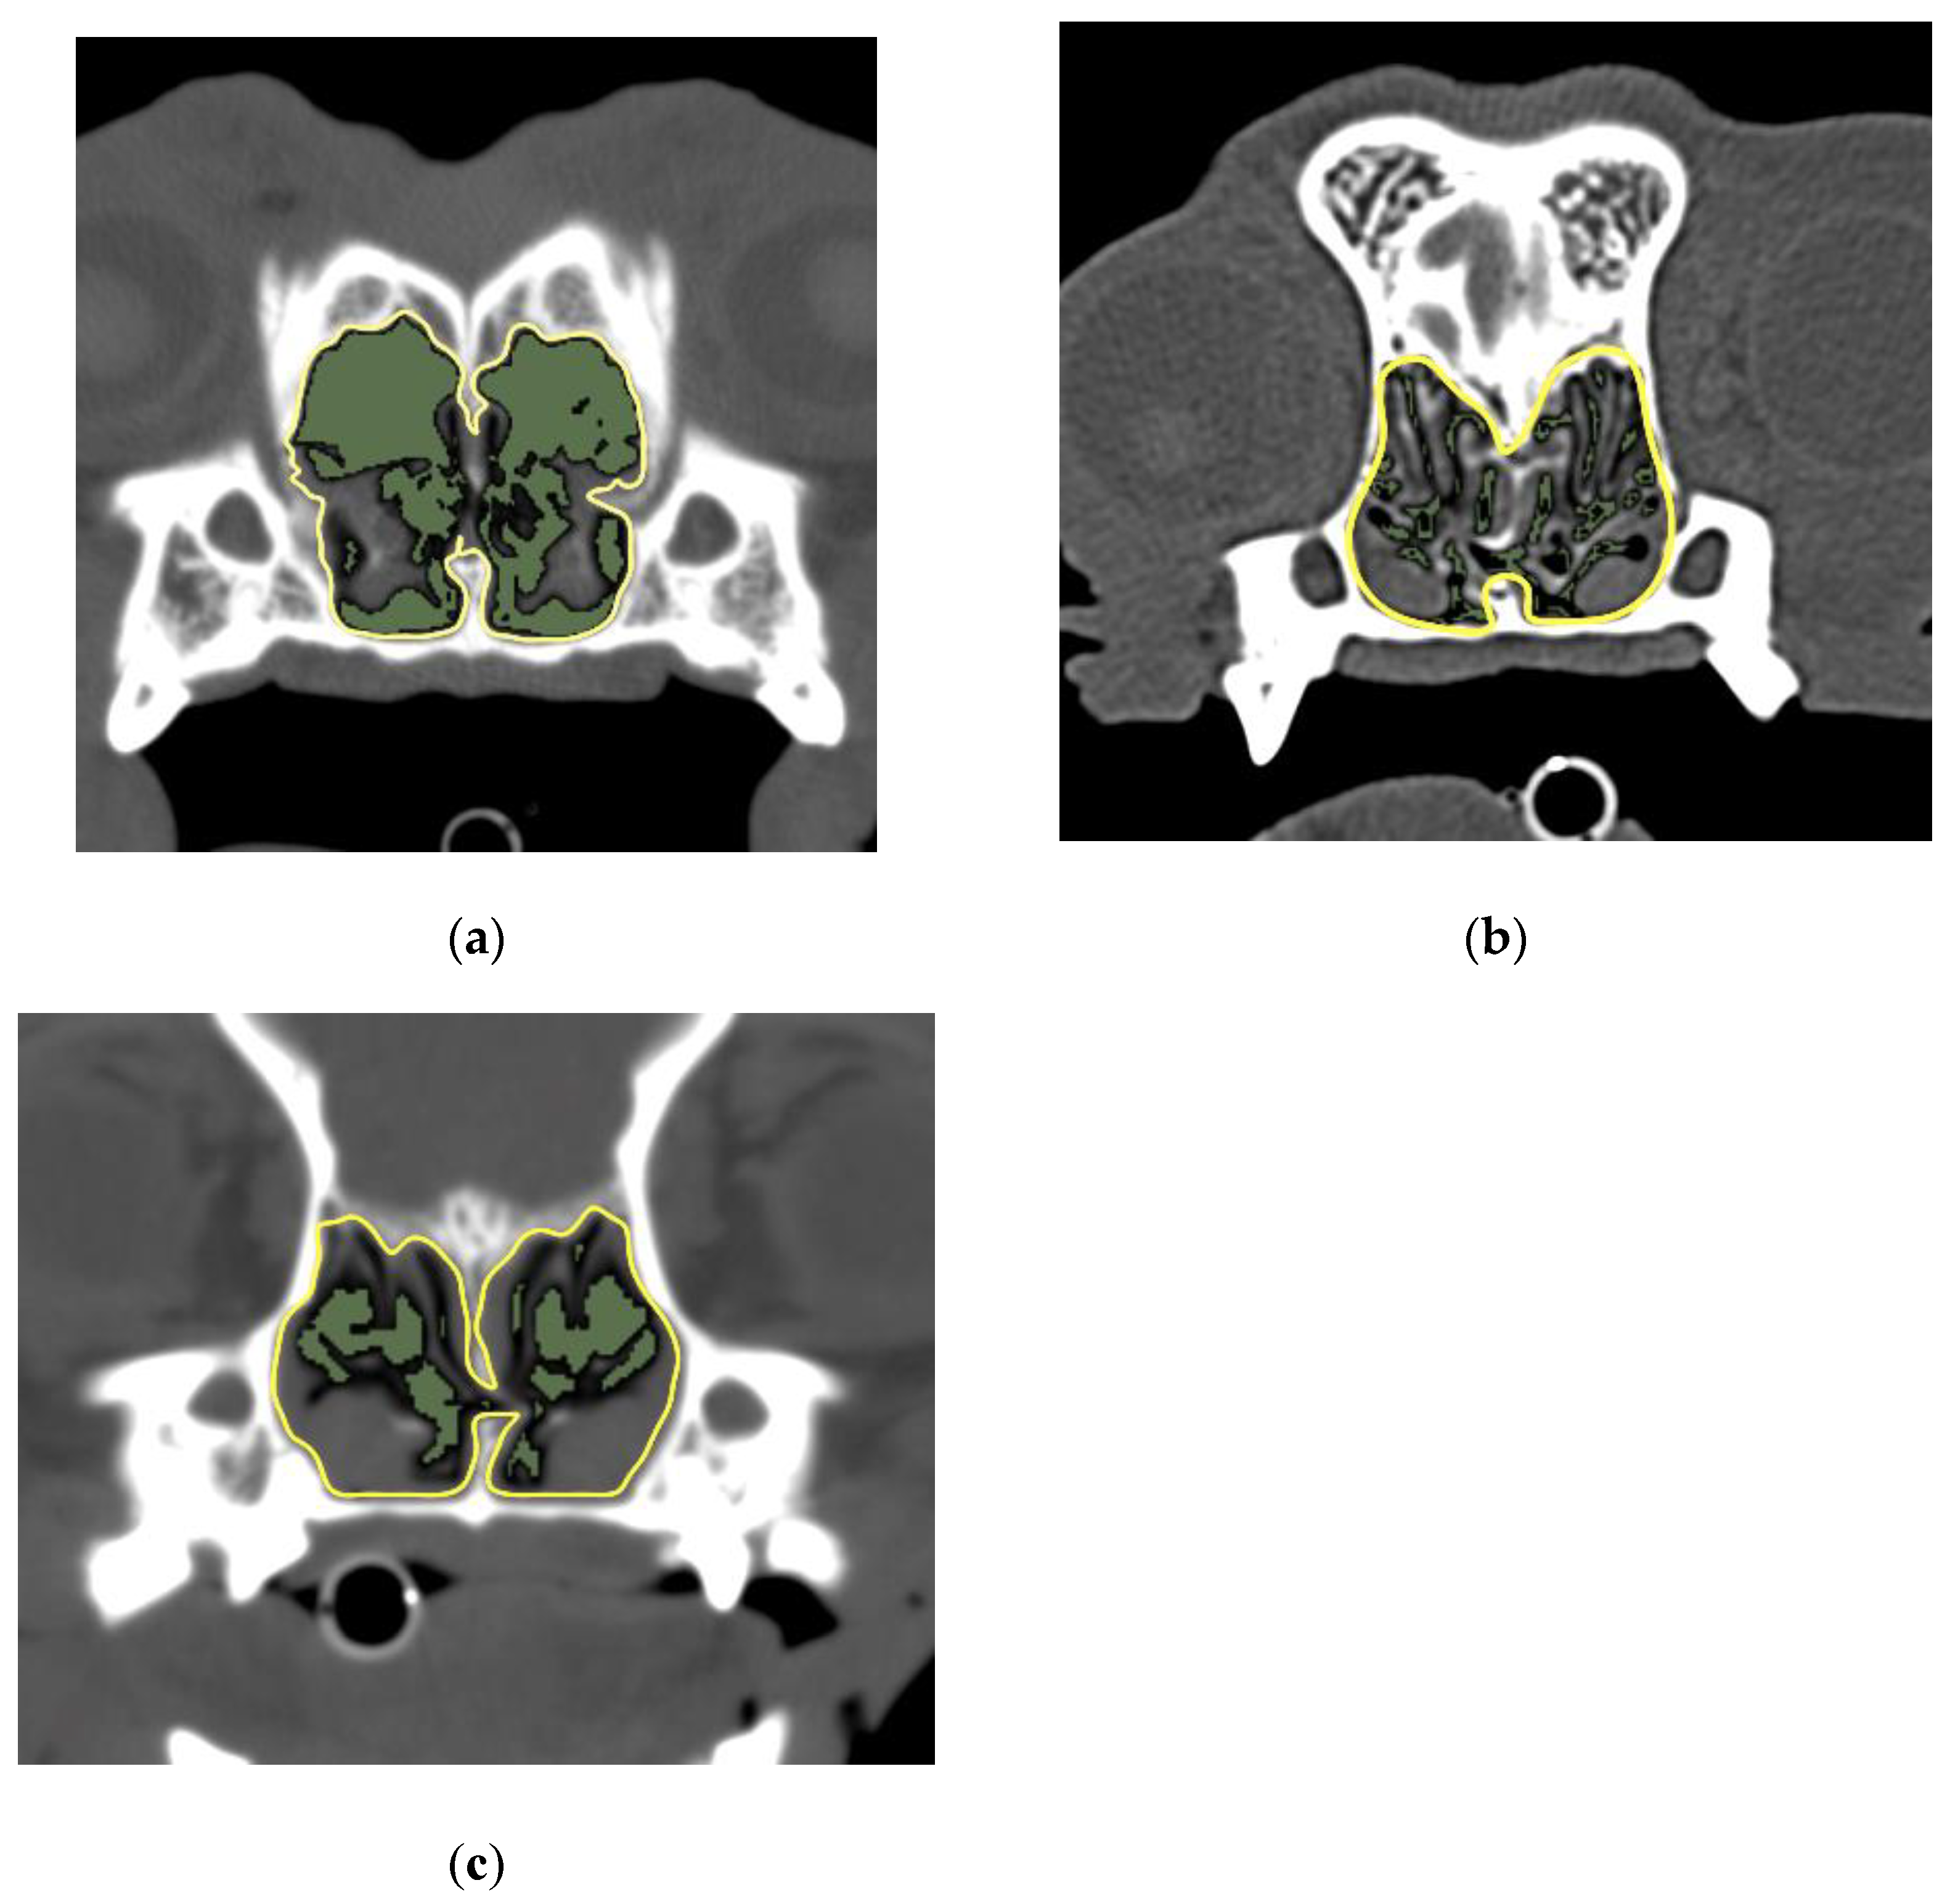

2.3.1. 2D Region Growing

2.3.2. Measurement of the AA/NC Ratio